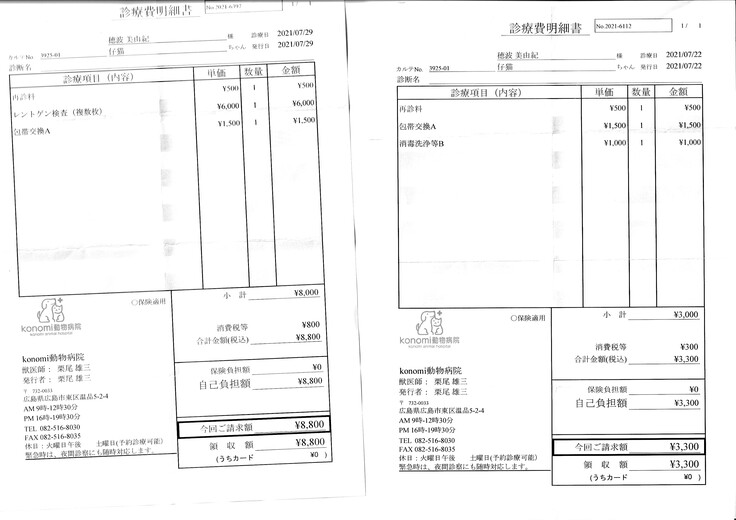

明細書

②退院後の飼育と治療

治療は続いていますが、これまでにかかった費用の一部を皆さまに助けて頂きたく、宜しくお願い致します。